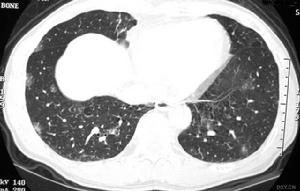

免疫缺陷性肺炎13.氧化代謝異常慢性肉芽腫病是吞噬細胞內氧化代謝異常的代表性疾病。吞噬細胞遭遇刺激如病原微生物入侵後不能提高氧耗,因而,不能產生超氧陰離子和過氧化氫,喪失氧化殺菌功能。常在10歲以內發病。皮膚、肺、骨骼和淋巴結最常受累。肺部感染表現包括瀰漫性浸潤、肺門淋巴結腫大或肺不張、肺膿腫形成、“局限性”肺炎等。病原體多為觸酶陽性菌如金黃色葡萄球菌和麴黴菌等,因為觸酶陽性菌破壞過氧化氫而使抗微生物防禦系統變得不完善。除針對病原體套用抗微生物藥物外,據報導Smzco對預防本病感染的發生有一定效果。感染灶的外科處理也是重要的。常規治療無效時可以輸注白細胞。感染是最常見死因,多數於兒童期夭亡,但也有生存至30歲以上者。氧化代謝異常的另一種疾病是萄萄糖-6-磷酸脫氫酶缺乏。臨床特點是溶血性貧血和反覆感染,主要為葡萄球菌和某些革蘭陰性桿菌感染。